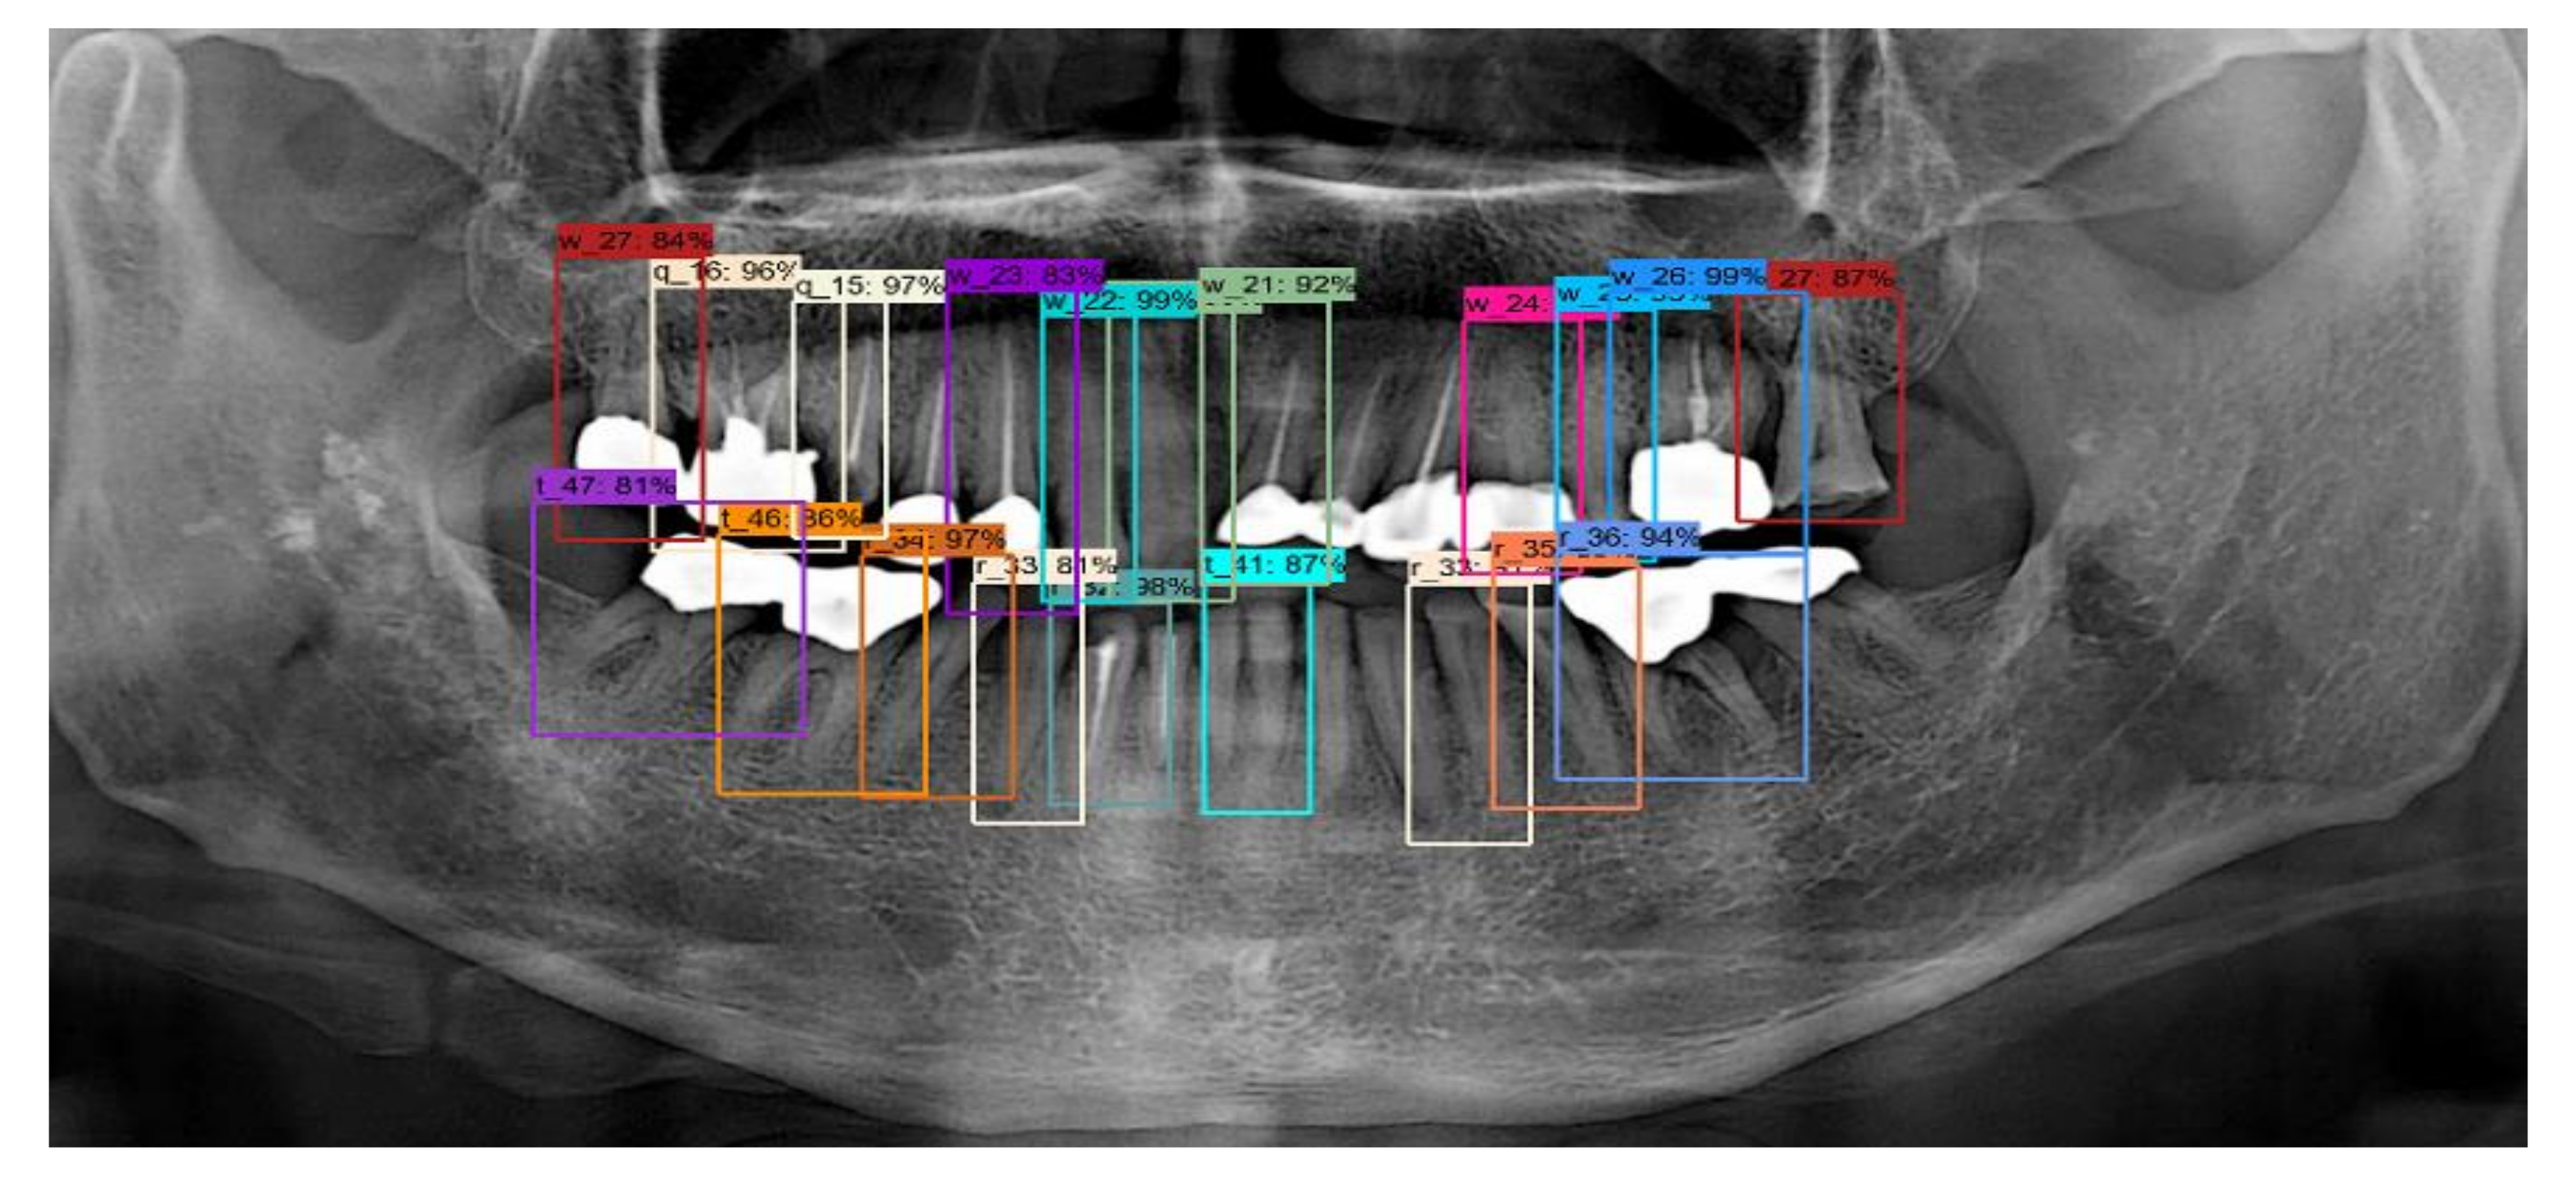

Table 3 shows that the probability of a tooth actually existing in the location indicated by the RCNN algorithm was 84.2%, with a sensitivity of 75.5%, and a precision of 84.5%. In addition, for tooth numbering, an accuracy of 77.4% was consistently obtained between the location of the actual tooth and the location indicated by the algorithms. The results of tooth detection are shown in Figure 10. As shown in this figure, all information about the position of the tooth can be detected correctly. However, it can be seen that the small tooth and crown cannot be detected for the tooth whose shape is not recognized.

Figure 10. Results of tooth detection.